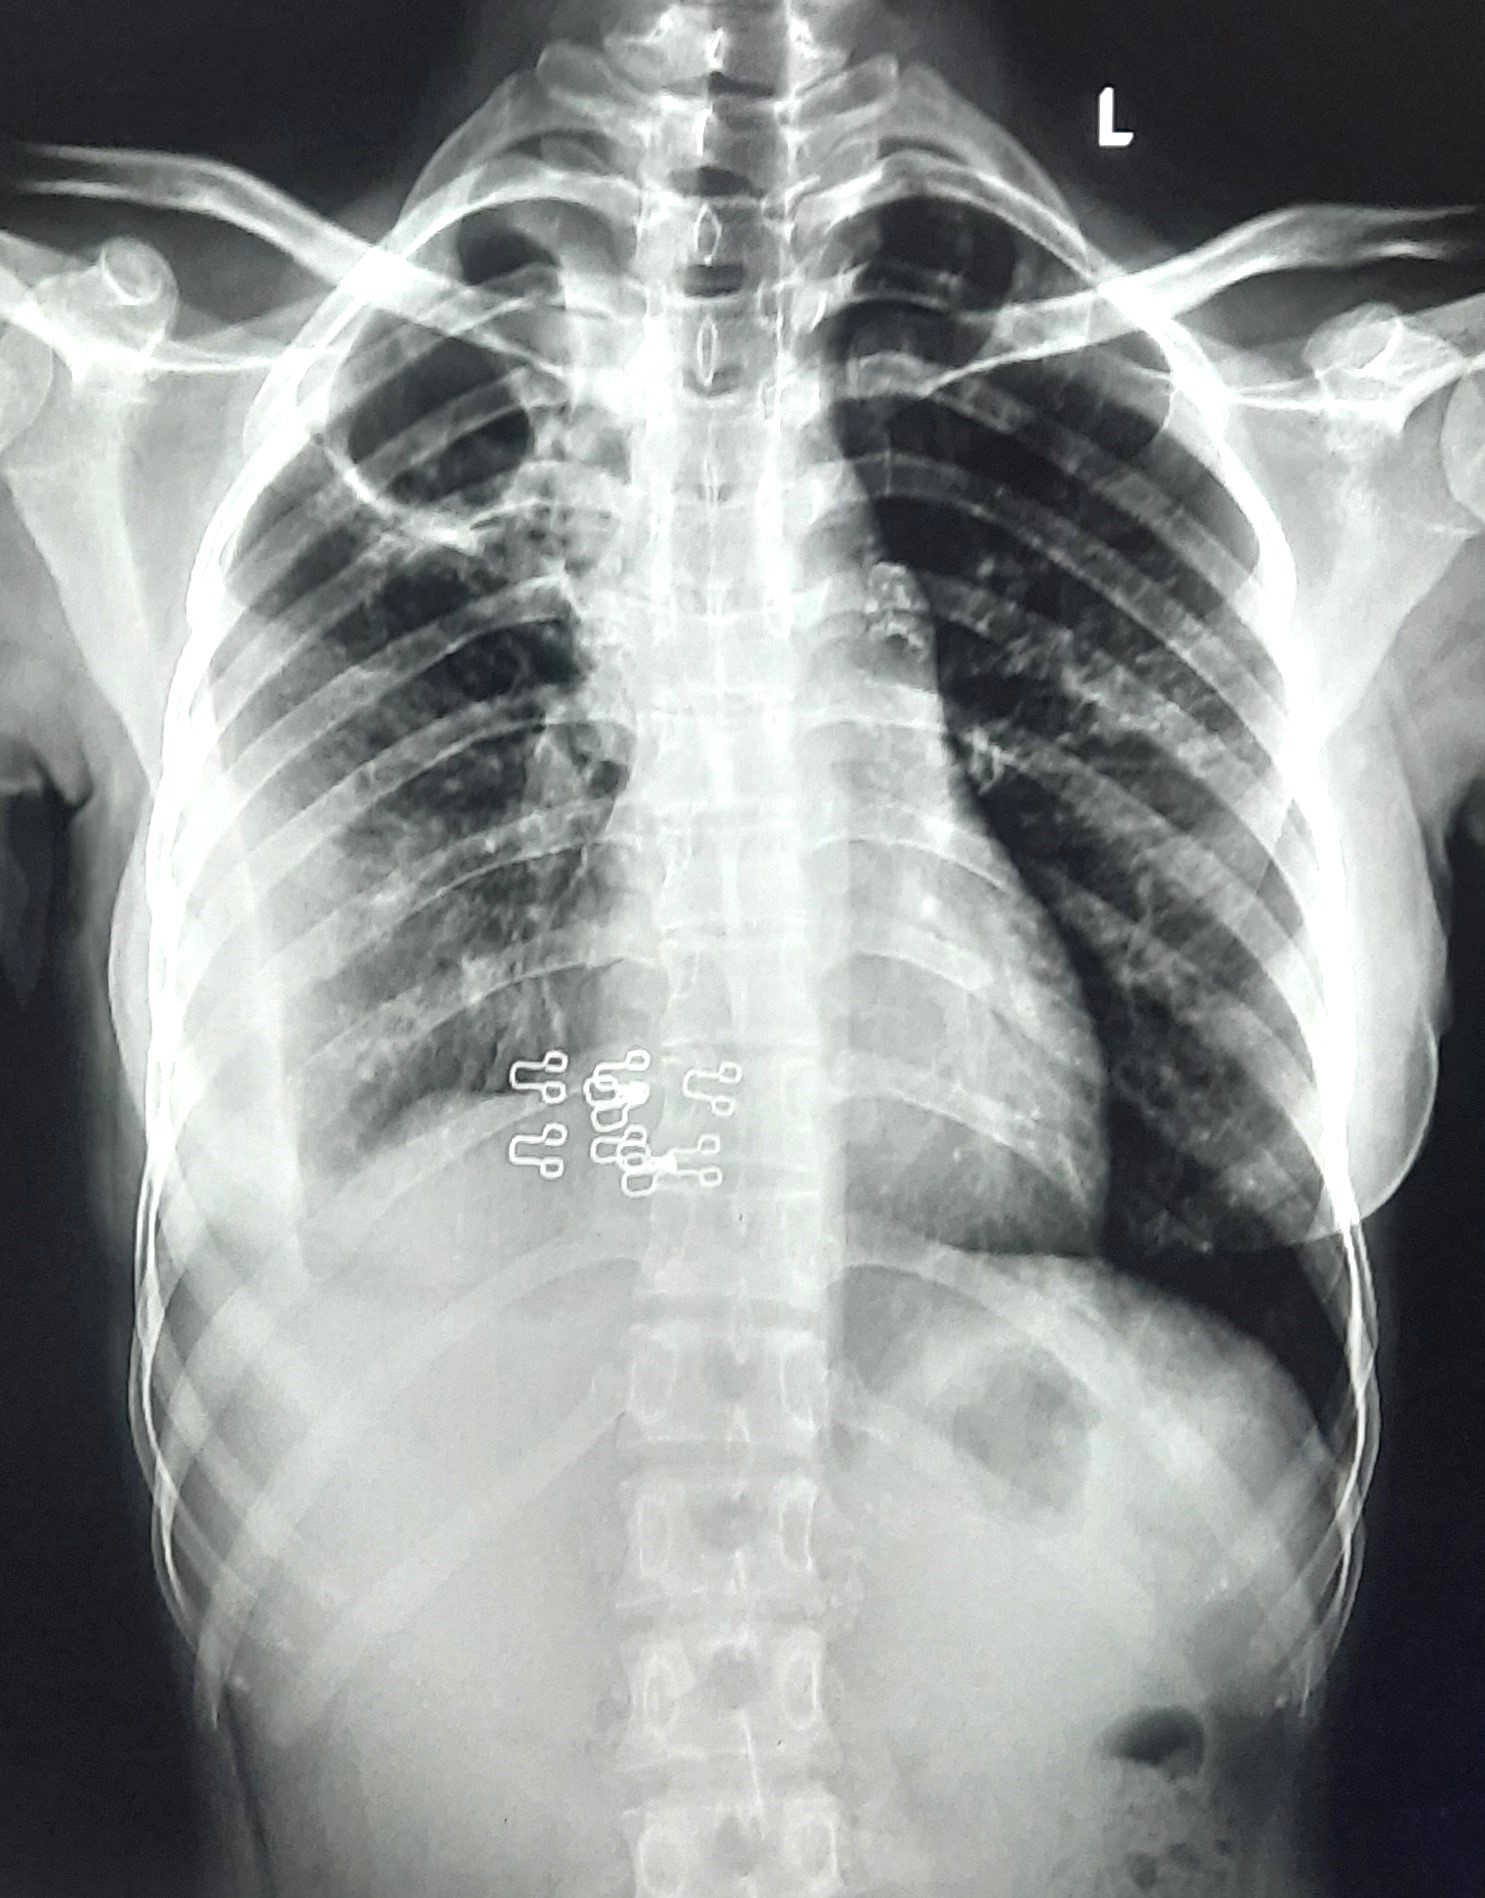

| 158 | IGGMC, Nagpur, Nagpur | P2 | 29-4314 | Subhash Bhoyar | Consent taken on Paper | 63 Yrs. |

Provisional Diag : Pulmonary Tuberculosis Follow-Up

Final Diag : Pleural Effusion |

TB Case (Confirmed) | Bilateral CP Angle Blunting | Abnormality visible on x-ray |